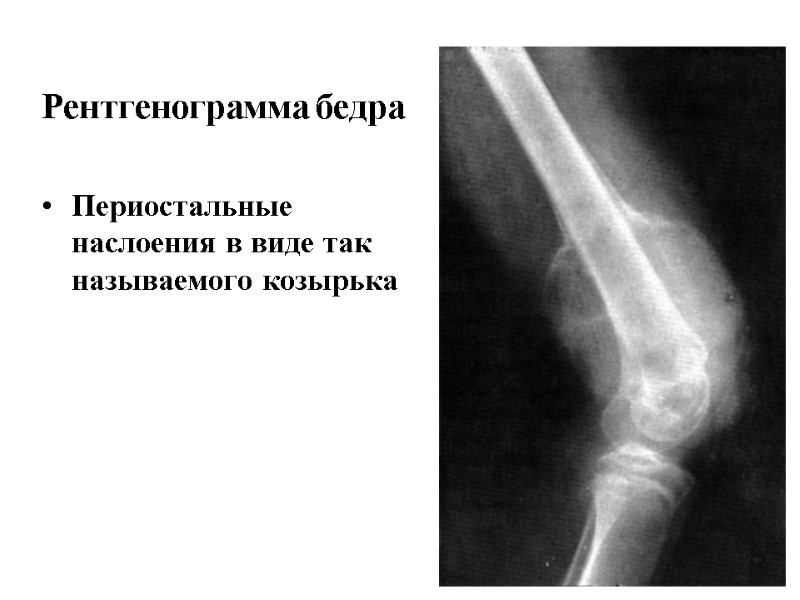

Рентгенограмма бедра Периостальные наслоения в виде так называемого козырька